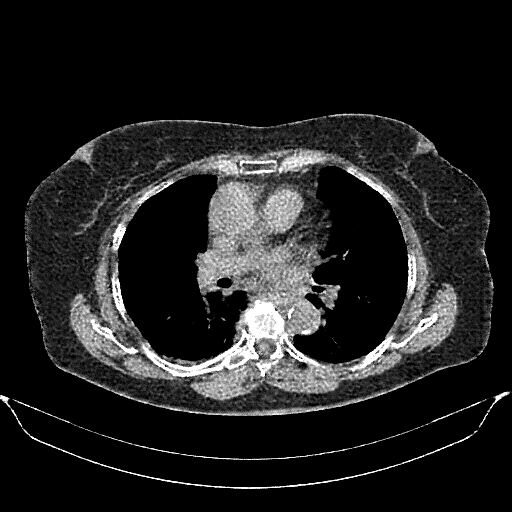

Original VENOUS CT scan

No window - Raw intensity values

Lung window (WL -600, WW 1500 β†’ Low βˆ’1350, High +150)

Mediastinum window (WL 40, WW 400 β†’ Low βˆ’160, High +240)